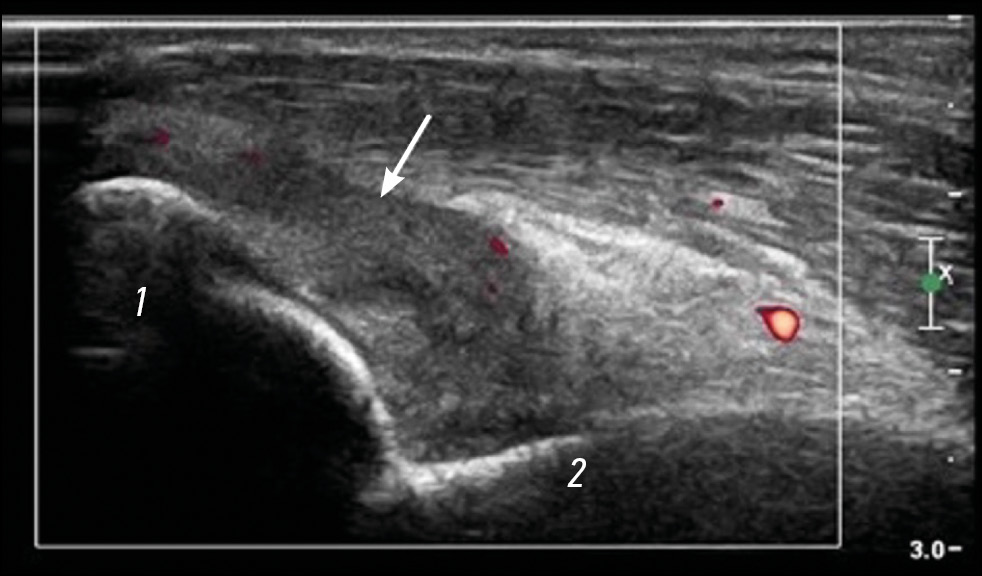

Hyaline cartilage is affected by interleukin (IL) 1β, IL- 6, and tumor necrosis factor-α (TNF-α), which can lead to chondrolysis and, subsequently, to arthralgia or progression of osteoarthritis in some patients (Fig. 4).

Fig. 4. Arthritis of the elbow joint, longitudinal sonogram. The joint capsule is hypertrophied mainly owing to the synovial membrane (arrow). Intense blood flow is observed in the synovium. Practically no fluid component is visible in the joint cavity. 1 — olecranon; 2 — humerus.